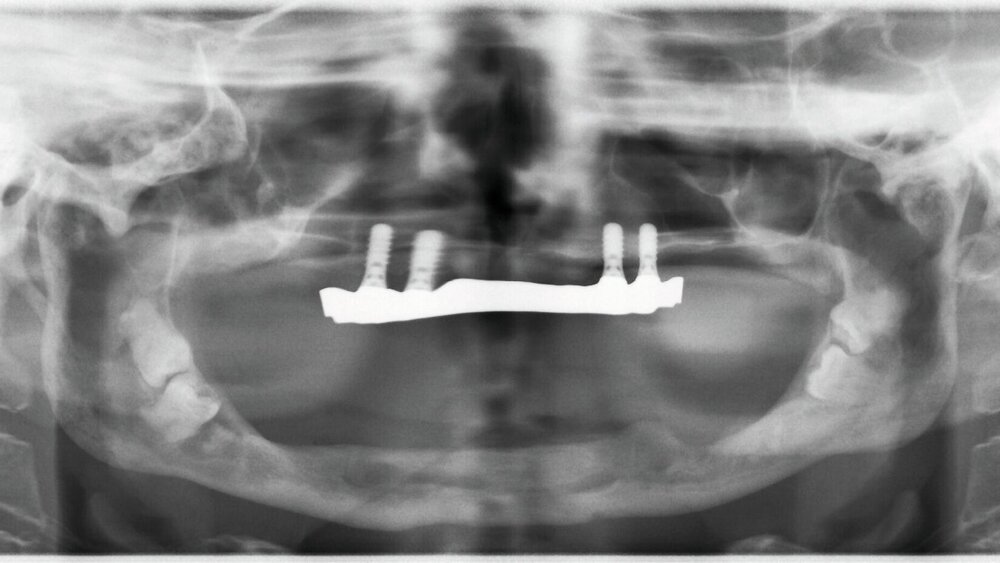

In der Panoramaschichtaufnahme sind beidseits in den aufsteigenden Ästen des Unterkiefers verlagerte Zähne 39, 38, 48 und 49 zu erkennen (Abbildung 1). Der anteriore Alveolarfortsatz erscheint in der zweidimensionalen Projektion ausreichend hoch zu sein.